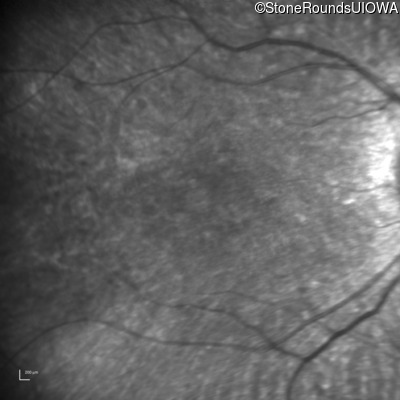

Infrared Fundus Photograph - Right - 20/80 -1

Exemplar